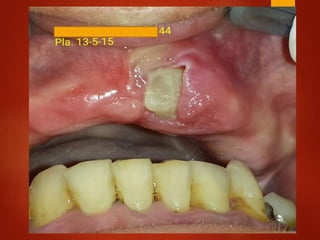

El documento es un registro médico odontológico que muestra las fechas de las visitas de un paciente al centro de salud El Raval, incluyendo exámenes y tratamientos realizados como la extracción de cálculos salivales en abril y mayo de 2012.